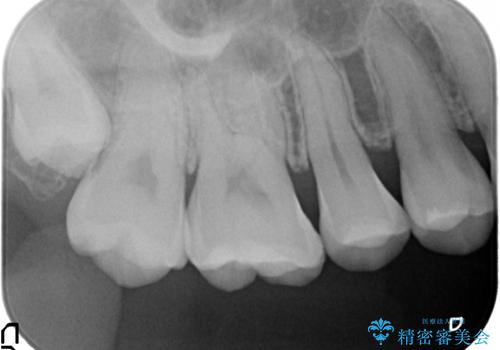

- 冷たいものを飲むと右上の奥歯がしみるので診て欲しいといらっしゃった方の症例です。

右上6番目、7番目の歯の樹脂が劣化していたため、虫歯除去後セラミックインレーによる修復を行いました。